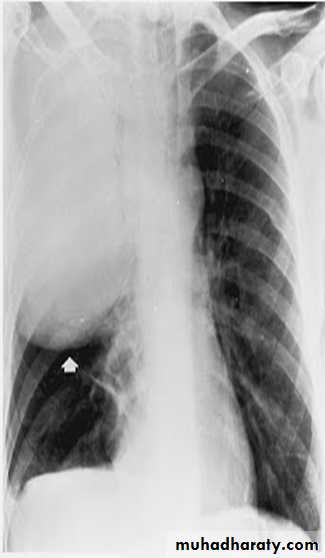

Lobar pneumonia

PA chest x-ray shows consolidation in the left lung base. A lateral view was obtained and shows that the consolidation is located posteriorly. Lateral view are especially important in showing infiltrates, which may be obscured by the heart on PA view.

• Lobar pneumonia: Patchy opacification evolves into homogeneous consolidation of affected lobe. Air bronchogram (air-filled bronchi appear lucent against consolidated lung tissue) may be present